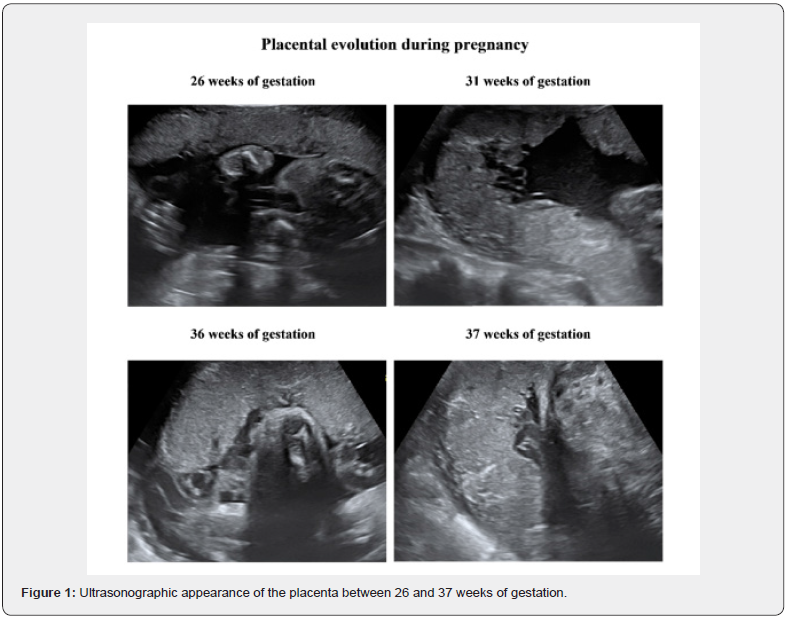

Placenta is a very dynamic organ whose morphological and functional integrity is the key factor for a normal developing foetus. Ultrasonographic appearance of the placenta is very much dependent on gestational age. Different aspects are normally seen in different weeks of gestation. According to well-known ultrasound Grannum classification there are 4 different grades of placental evolution during pregnancy. In grade 0 the placenta has a uniform echogenicity and a smooth chorionic plate whereas in grade III the extensive calcium deposits resemble deep indentations and ring-like structures. A representative example of placental evolution during pregnancy can be seen in zoomed format in figure 1.

Placental calcifications are often mentioned on ultrasound examination during pregnancy and seen as echogenic foci as the calcium is progressively deposed in the placental tissue [1]. Placental calcification is usually thought to represent a physiological process, a normal feature of aging and maturation [2]. Reports in the literature have shown that more than 50% of placentae had some degree of calcification and at least 18% showed excessive calcification [3]. Miller et al reported that grade III placental calcification was found in 39.4% of pregnant women at term [4].